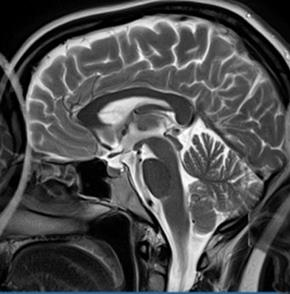

Na którym obrazie MR jest widoczne pasmo saturacji?

A. Obraz 2

B. Obraz 1

C. Obraz 3

D. Obraz 4